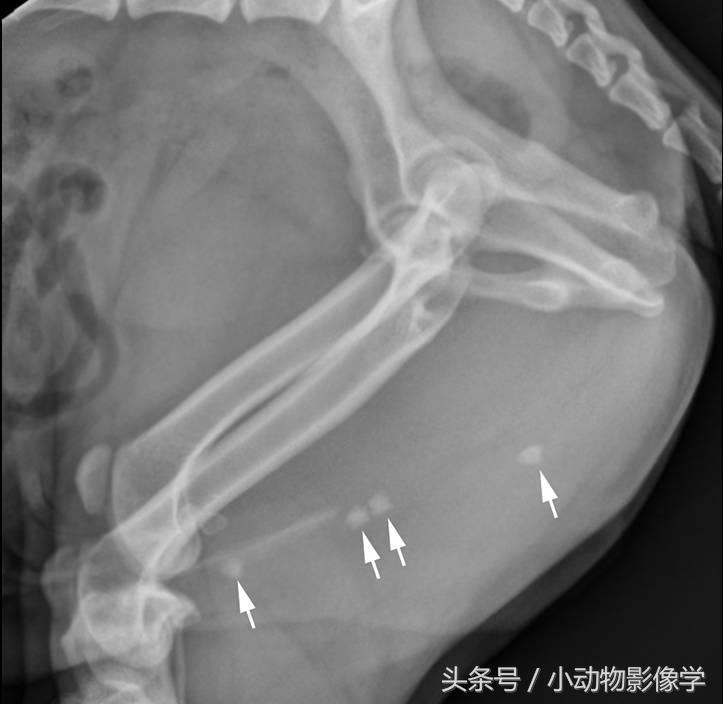

膀胱结石可能会下降到尿道,导致尿道阻塞。对于公犬,X光片拍摄必须调整位置,使影像涵盖整个尿道(图10)。

图10、一只公犬侧位平片,聚焦于会阴部,后肢向腹侧牵拉(后肢在髋股关节处弯曲)。该射线照片显示了尿道海绵体部多个界限清楚的不透明矿物结石(箭头)。